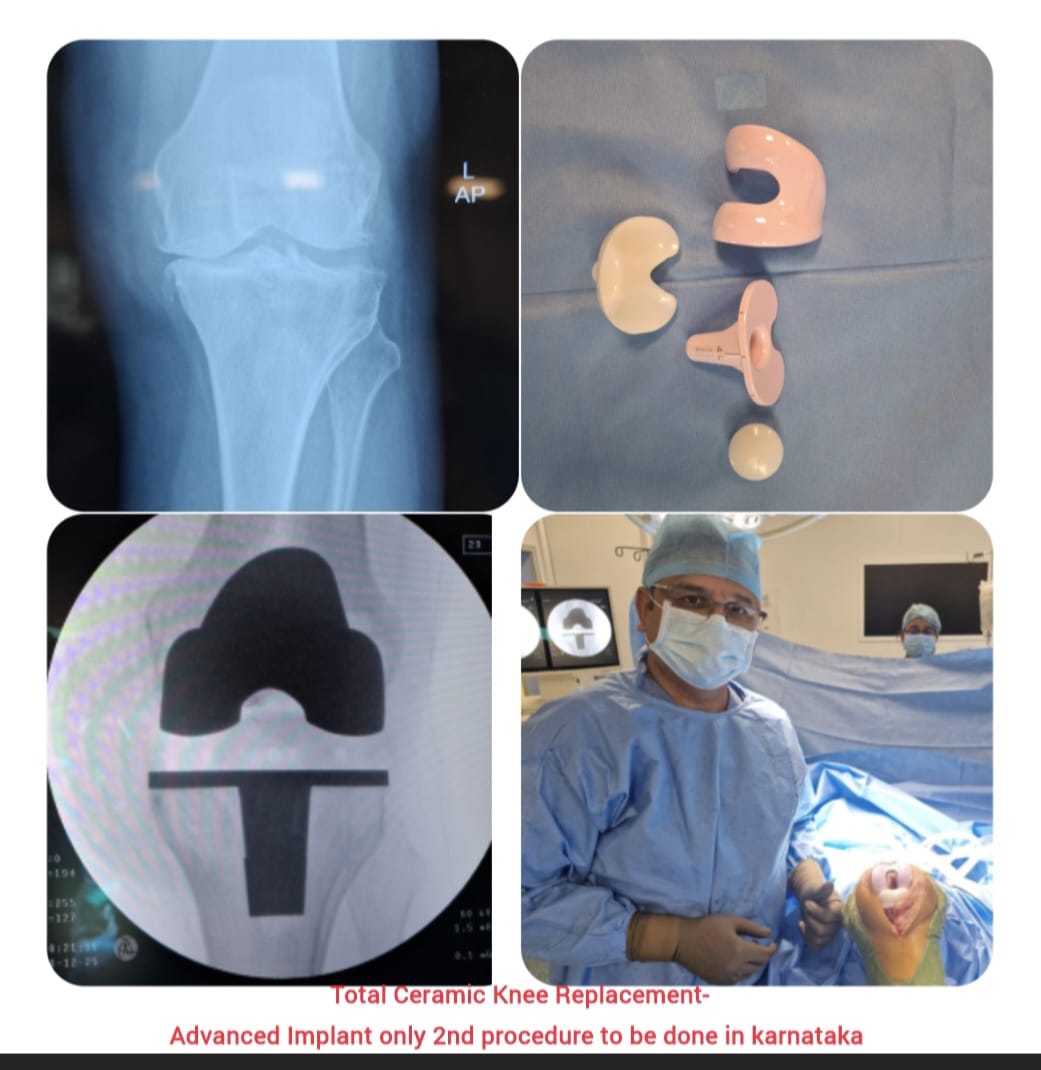

Knee replacement, also known as knee arthroplasty, is a surgical procedure performed to relieve chronic knee pain and restore joint function in patients suffering from advanced arthritis, severe joint damage, or deformities. The procedure involves replacing damaged cartilage and bone surfaces with durable artificial implants that restore smooth knee movement.

Knee arthroplasty is carefully planned based on the patient’s age, activity level, degree of joint damage, and overall health. Modern surgical techniques and advanced implant designs allow improved alignment, stability, and long-lasting outcomes with reduced postoperative discomfort.